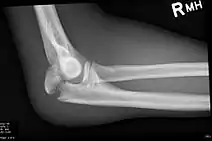

| Fracture of the olecranon | |

Olecranon fracture is a fracture of the bony portion of the elbow. The injury is fairly common and often occurs following a fall or direct trauma to the elbow. The olecranon is the proximal extremity of the ulna which is articulated with the humerus bone and constitutes a part of the elbow articulation. Its location makes it vulnerable to direct trauma.

To assess an olecranon fracture, a careful skin exam is performed to ensure there is no open fracture. Then a complete neurological exam of the upper limb should be documented.[5][2] Frontal and lateral X-ray views of the elbow are typically done to investigate the possibility of an olecranon fracture.[1] A true lateral x-ray is essential to determine the fracture pattern, degree of displacement, comminution, and the degree of articular involvement.